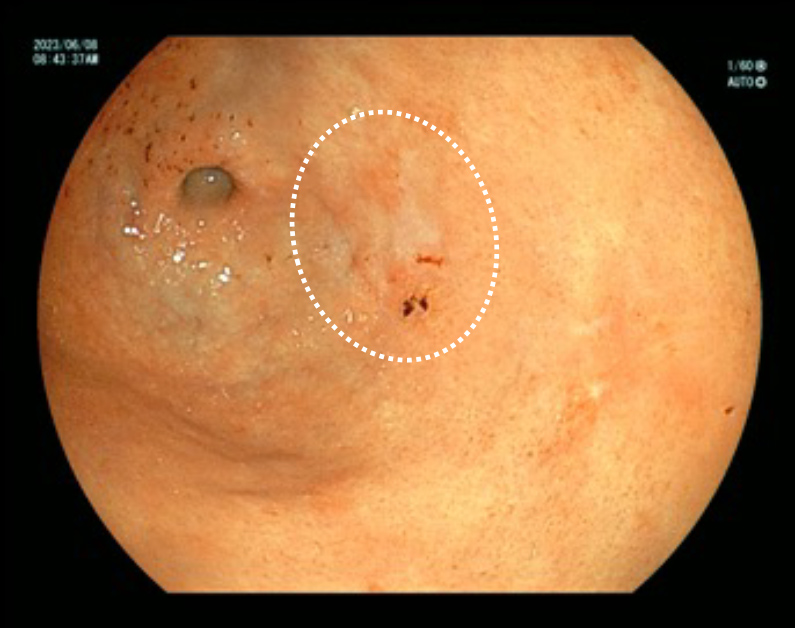

内視鏡検査の所見例

発赤した食道癌

内視鏡検査の所見例

発赤した食道癌